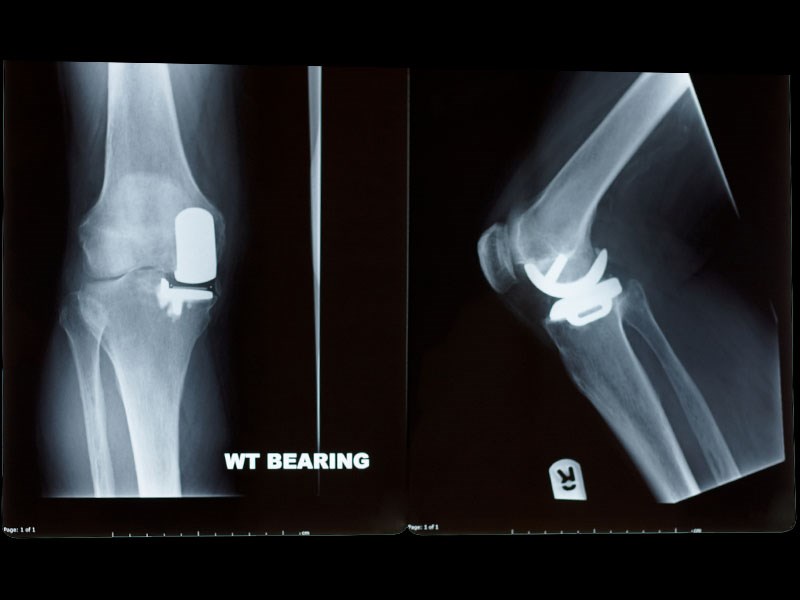

Joint Replacement Surgery

These pages are designed to give you the right information about some common joint replacement surgeries, along with some advice and exercises to help you with your rehabilitation.